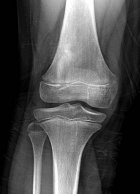

9 year old female c/o right knee pain. She began having pain four weeks ago. She describes the pain as sharp and moderate in intensity. It bothers her at rest and while sleeping.

Zoom image: Radiological image Radiological image.